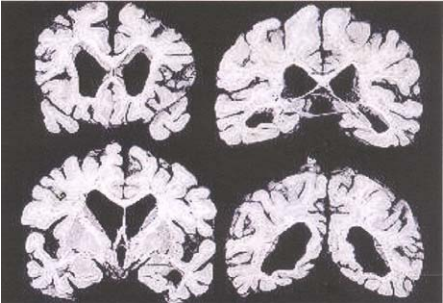

91 下圖所見有異狀的大腦,最符合那一種病況?

(A) 48 歲女性,表現多種會緩解又再發之不相關的神經學缺陷已經六年 (B) 78 歲病人,出現肌肉僵硬、動作遲緩及震顫 (C) 76 歲病人,有七年記憶力喪失、方向感喪失及失智的病史 (D) 53 歲男性,很快發作記憶力喪失、尿失禁及步態異常